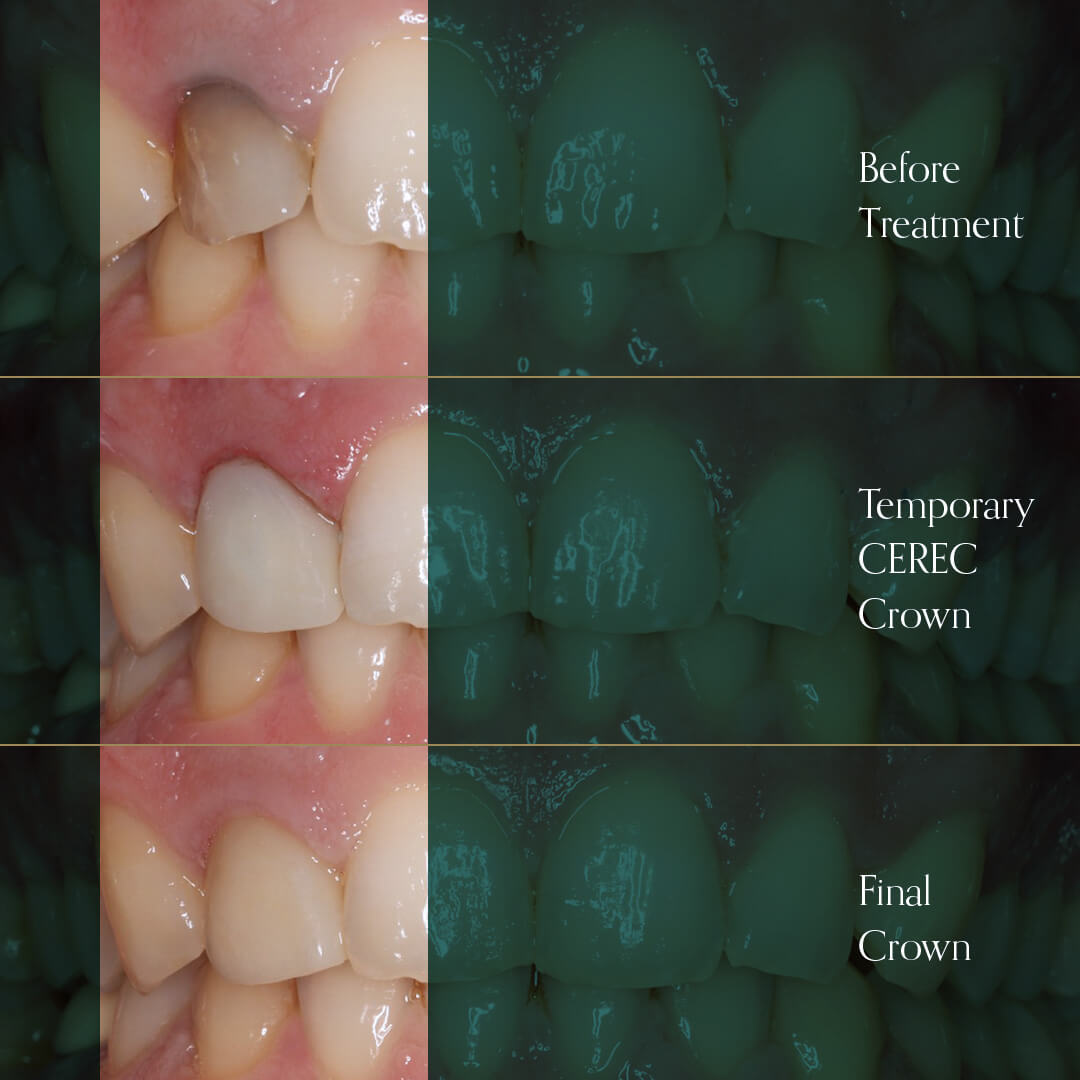

- Broken, chipped, worn out or damaged teeth

- Can also be used to mask discoloured teeth or straighten teeth using veneers

Our cosmetic dentists use their expertise and creative skills to produce quality restorations for a smile that is healthy, natural looking, and beautiful.